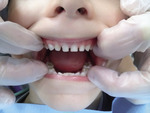

Głównym czynnikiem zapobiegającym powstawaniu płytki bakteryjnej, a tym samym obniżającym ryzyko wystąpienia ECC jest regularne szczotkowanie zębów. Wyniki badań wskazują, że dzieci z próchnicą mają statystycznie istotnie wyższe wartości wskaźników higieny.[8]

Oczyszczanie jamy ustnej należy wprowadzać jeszcze przed pojawieniem się pierwszych zębów, delikatnie przecierając je wilgotną gazą lub tetrową pieluchą.[9] Można je też wykonać za pomocą silikonowych nakładek na palec.

Szczotkowanie zębów szczoteczką wprowadza się w momencie pojawienia się pierwszego zęba, najpóźniej około 1. r.ż. Powinno odbywać się ono przynajmniej dwa razy dziennie, koniecznie przed snem nocnym, a według niektórych nawet po każdym karmieniu.

Wyniki badań wskazują, że późniejsze rozpoczęcie wykonywania zabiegów higienicznych w jamie ustnej dziecka wiąże się z wyższą frekwencją próchnicy. W badaniach Szczepańskiej i wsp.[24] u dzieci, u których wprowadzono je przed 12. m.ż., liczba puw wynosiła 3,61, a u tych, u których oczyszczanie rozpoczęto później, aż 5,53. Podobną zależność odnotowali też inni badacze.[29,32] Wpływ miała również częstotliwość szczotkowania. Płytkę stwierdzono prawie dwukrotnie rzadziej u dzieci szczotkujących zęby dwa razy dziennie w porównaniu z tymi, które robiły to sporadycznie.[23] Z badań innych autorów wynika, że szczotkowanie zębów dwa razy dziennie i częściej znacząco obniża wartość liczby puw. Może to mieć większy wpływ na ograniczenie występowania próchnicy u dzieci w wieku 1,5-4,5 lat (ryc. 1) niż zmniejszenie podaży cukrów.[30]

Do interesujących wniosków doszła Paunio[33], która wykazała wprost proporcjonalną zależność częstości szczotkowania u dziecka od tego, jak regularnie wykonują tę czynność rodzice. Ich udział w higienie dzieci nie podlega dyskusji. Mimo że już w 2. r.ż. wprowadza się naukę samodzielnego oczyszczania jamy ustnej, to do 7. r.ż., a według niektórych nawet do 10. r.ż., za jej jakość odpowiadają rodzice. Efektywne samodzielne szczotkowanie zależy od sprawności manualnej dziecka, którą osiąga ono dopiero około 8.-10. r.ż. Poniżej 8. r.ż. jest nieskuteczne, mimo że wielu rodziców uważa to za dowód jego samodzielności. Dwulatek będzie próbował sam szczotkować i trzeba mu na to pozwolić, ale nie należy oczekiwać, że wykona to prawidłowo. Muszą zrobić to za niego rodzice.